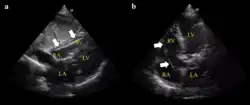

Setup for doing an ECG off the device

Example of ECG off the device a) free floating in the RV b) in contact with the RV wall